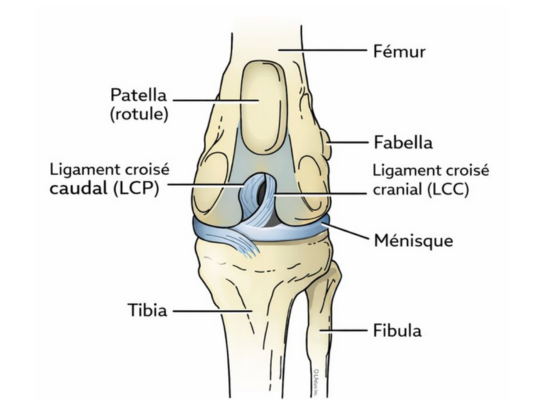

Vue de face du genou

Le genou du chien, ou grasset, est une articulation complexe composée de tendons, cartilage, ménisques et ligaments. Les ligaments croisés, situés au centre du genou, contrôlent les mouvements d’avant en arrière et la rotation.